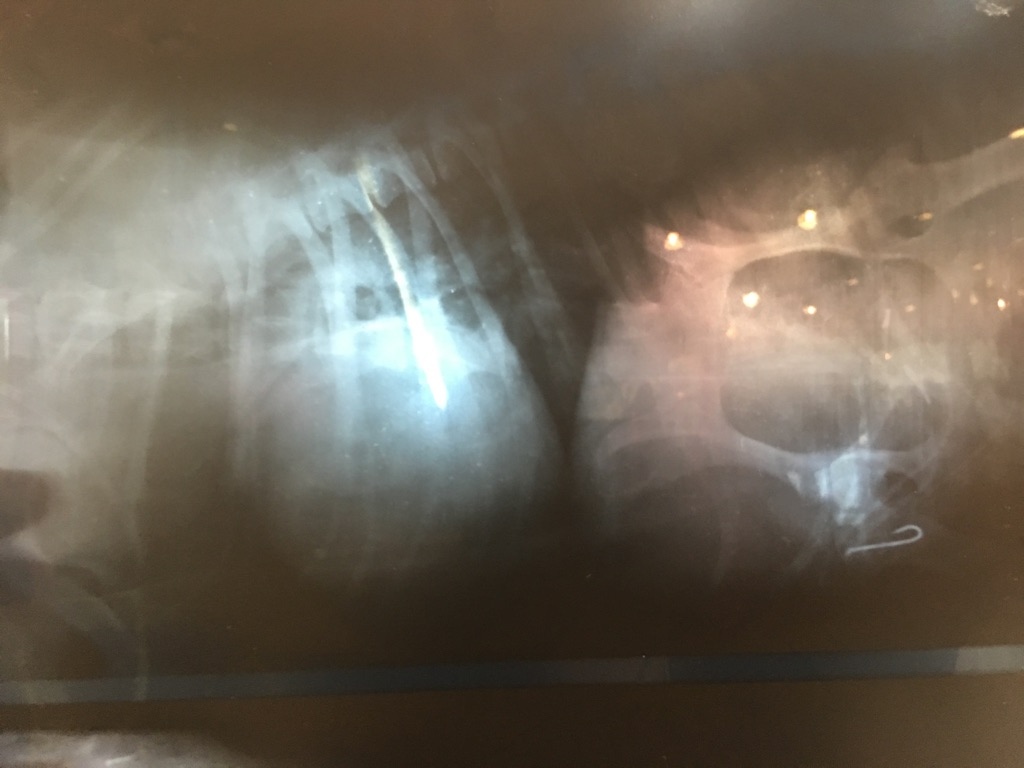

朝一病院のボス君。

結局、自力の排出は出来ずに、釣り針は動いてないので、夕方から内視鏡〜開腹手術になりました…( ; ; )

釣り針は体内で引っかかり、自力排出は難しいそうです。

誤飲は本当に怖いです。